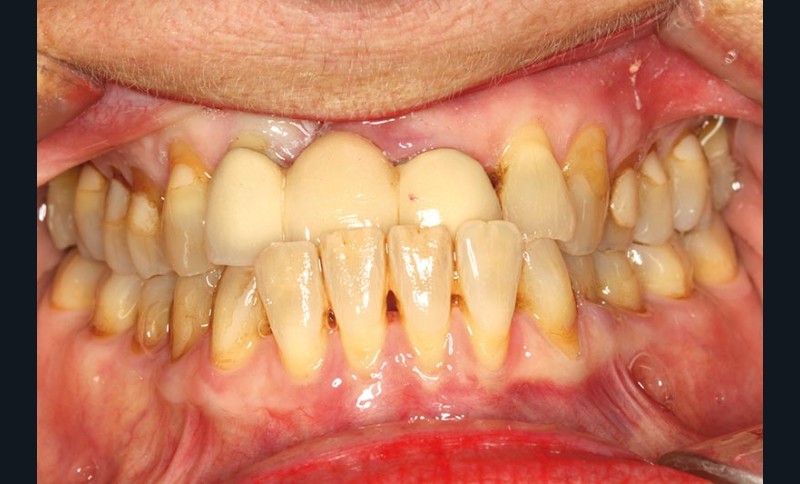

Une patiente présente un proglissement mandibulaire aboutissant à une inversion d’occlusion au niveau des incisives (fig. 2).

Au-delà du préjudice esthétique, il induit des forces importantes en direction vestibulaire sur les incisives mandibulaires. Ces incisives présentent une légère mobilité. La radio rétro-alvéolaire montre un élargissement desmodontal et une perte osseuse verticale sans cratérisation ni inflammation (fig. 3).

Un montage en articulateur des moulages permet d’observer en relation centrée (RC) de meilleures conditions d’affrontement des dents antérieures. La proposition thérapeutique est la réfection du bridge existant, une équilibration occlusale par coronoplastie des secteurs postérieurs pour stabiliser les appuis occlusaux en RC et la mise en place d’une contention dans le secteur antérieur mandibulaire. Une maquette prothétique permet la réalisation d’un bridge provisoire dans une position corrigée (fig. 4).